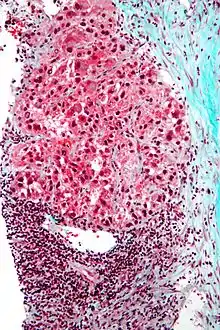

Mallory bodies in hepatocellular carcinoma. Trichrome stain.